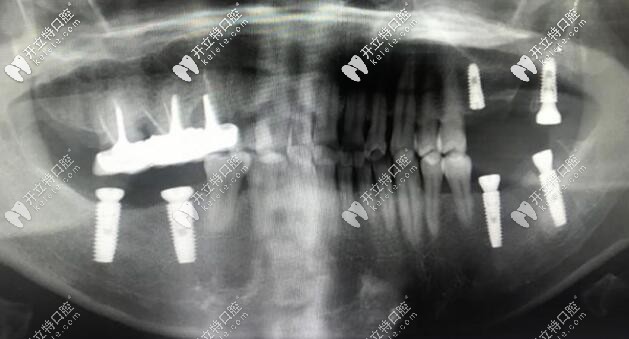

我看了一眼時間:6顆種植體不到半個小時,平均一顆不到十分鐘,這個速度是佩服的。

這種植后的樣子的,當然種牙的第二、三步還沒做的,但是我想比較困難的已經完成了, 后面帶牙冠只要聽醫(yī)生的就好啦!